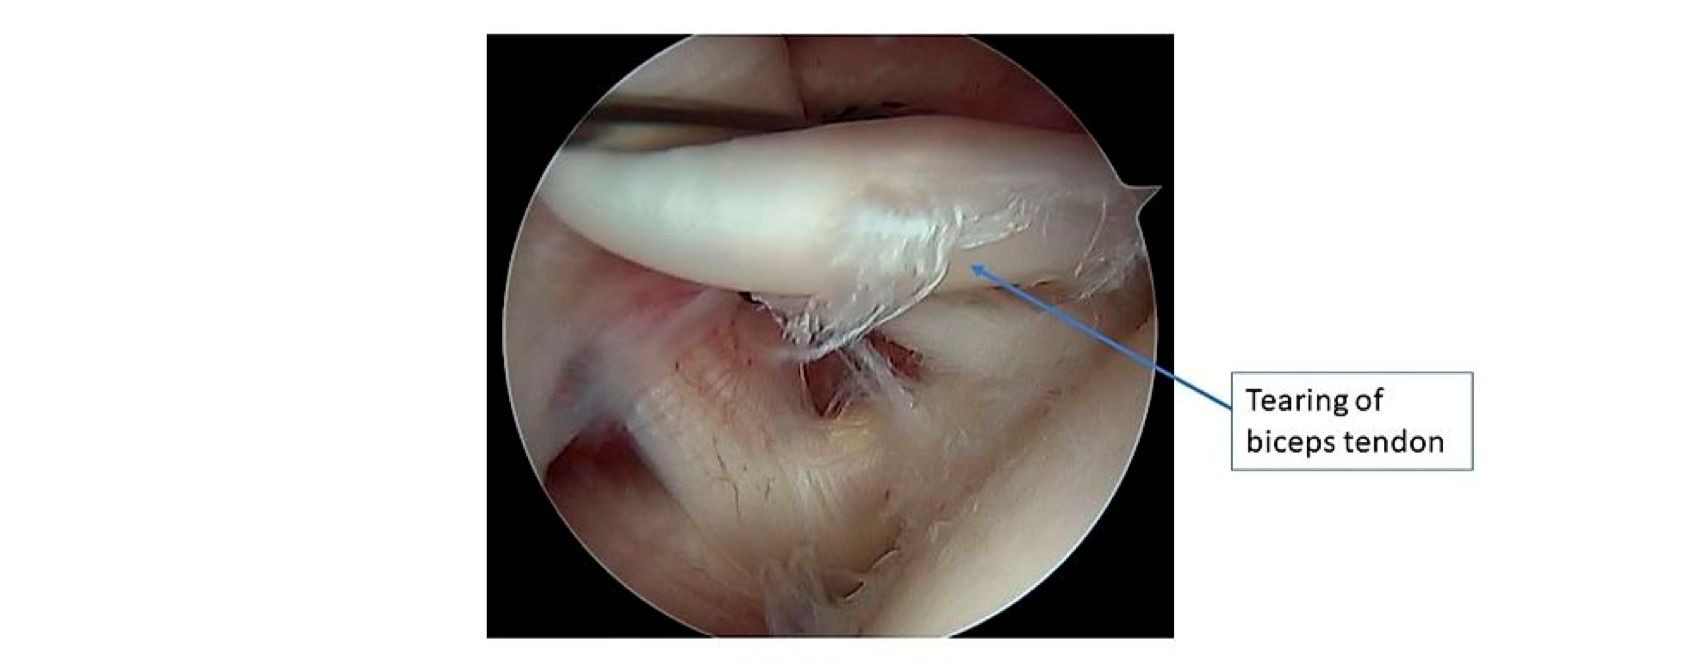

Arthroscopic image inside the shoulder joint.